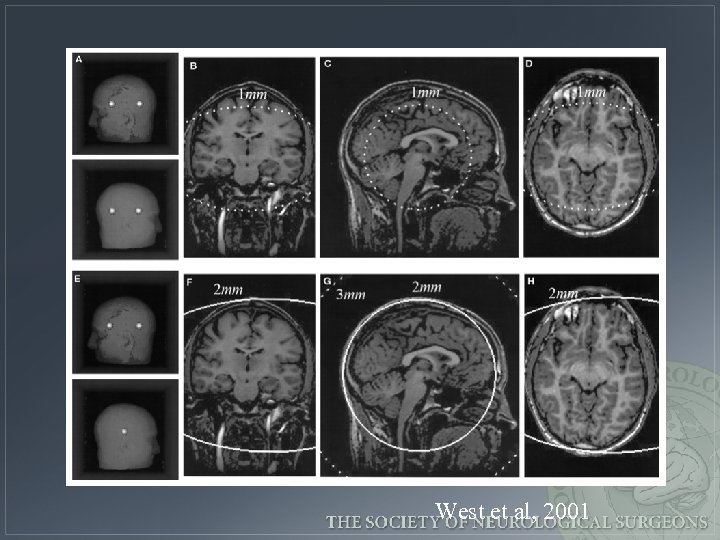

West et al, 2001

Error increases as the distance of the target from the fiducial centroid West et al, 2001

Tips regarding fiducials 1. Avoid linear fiducial configurations 2. Arrange fiducials so that the center of their configuration is close to the region of interest during surgery 3. Spread out the fiducials 4. Use as many fiducials as reasonably possible 5. Mark scalp at fiducial site 6. Avoid occipital region or distorted scalp partially adapted from West et al, 2001